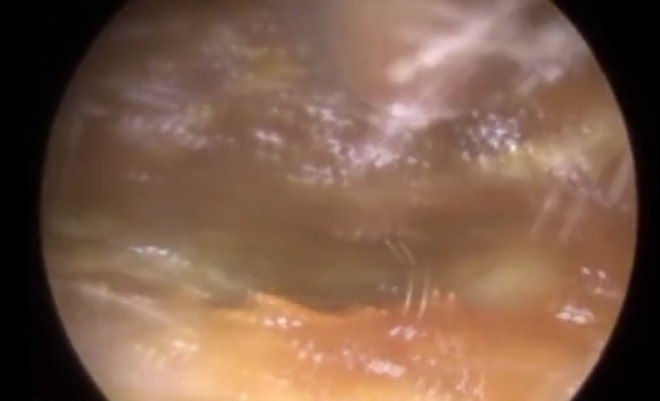

Um paciente recebeu a duvidosa honra de ter "a maior cera de ouvido do mundo" retirada de si em imagens grotescas gravadas pelo médico Neel Raithatha, em Leicestershire, na Inglaterra

O doutor utilizou um bisturi para retirar a massa de cerca de 2,5 cm de comprimento

O feito é ainda mais impressionante ao levarmos em conta que o tamanho médio do canal de um ouvido é de 3 cm

Raithatha utilizou um equipamento de sucção para remover os restos de cera que ainda bloqueavam os ouvidos do rapaz

"Felizmente, o ouvido dele ficou intacto e ele passa bem", afirmou o médico